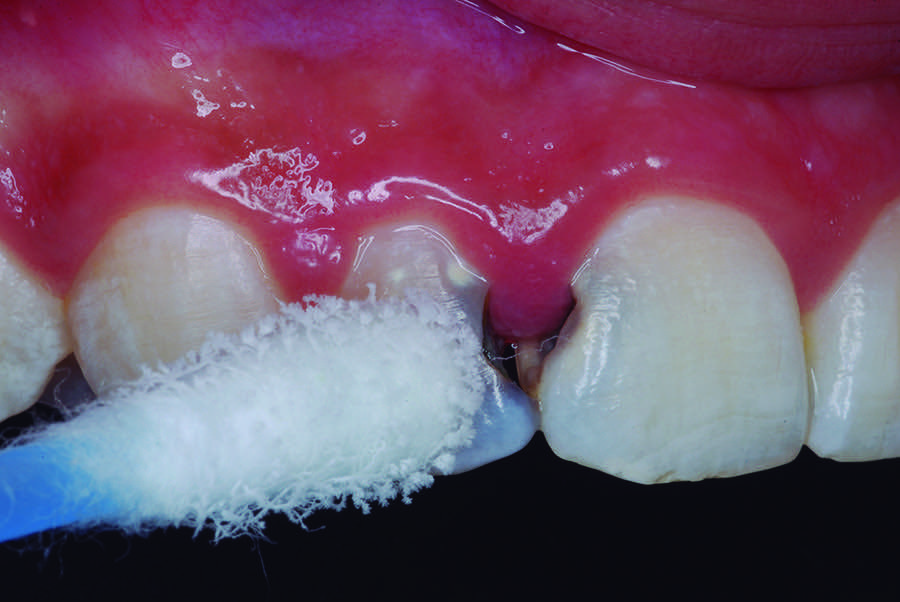

A 12-year-old male presented with extensive carious lesions observed on teeth Nos. 7 through 10, which were accompanied with gingivitis (Figure 1). The pulpal condition was verified through thermal sensitivity tests and vertical percussion, both being satisfactory (Figure 2). The proximity of the lesions with the pulp chamber and the absence of periapical lesions, especially in the right lateral incisor, were observed by the radiographic examination (Figure 3).

Fig 1. Initial aspect showing decayed teeth and gingivitis.

Figure 1

Fig 2. Thermal sensitivity test.

Figure 2